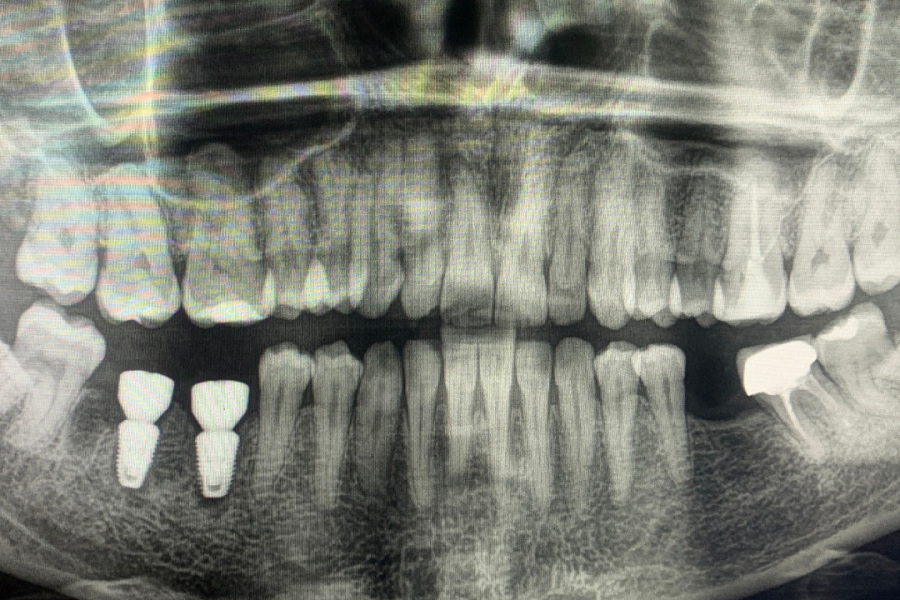

Пациентка обратилась с жалобой на перелом зуба, который ощутила при накусывании.

Провели имплантацию при помощи хирургического шаблона, который позволяет максимально точно спроектировать и спозиционировать положение имплантата для будущей функциональной нагрузки, грамотного распределения давления на имплантаты, а также здоровья зубного импланта. Операция прошла успешно.